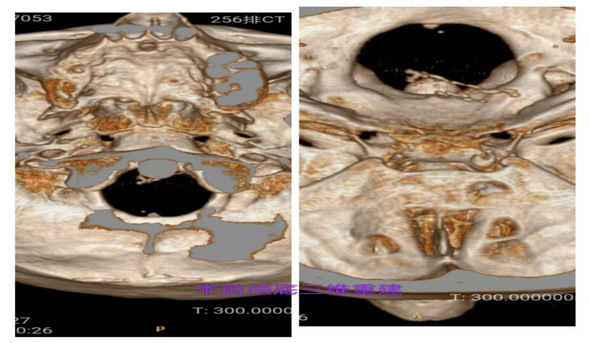

术前三叉神经MRI提示基底动脉移位压迫左侧三叉神经根部

颅底三维CT重建提示卵圆孔形态大小正常